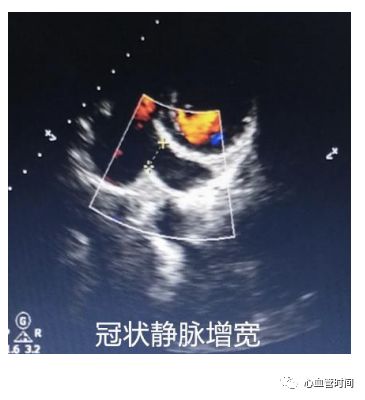

冠状静脉正常冠状静脉在长轴切面上看基本是个

「点」,增宽时要结合其他切面

测量内径大小并分析病因。

冠状静脉正常冠状静脉在长轴切面上看基本是个

「点」,增宽时要结合其他切面

测量内径大小并分析病因。

冠状静脉窦探头下压可见冠状静脉自左向右回流至右房,观察有无增宽。

冠状静脉窦探头下压可见冠状静脉自左向右回流至右房,观察有无增宽。